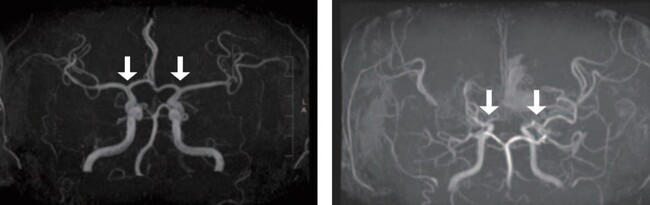

소아 모야모야병은 뇌로 혈액을 공급하는 혈관이 특별한 원인 없이 점차 좁아지는 만성 진행성 뇌혈관질환이다. 이 질환이 있으면 부족한 혈류를 보충하기 위해 비정상적인 미세혈관이 형성되는데, 이들은 혈류를 충분히 공급하기 어렵고 파열되기 쉬워 뇌경색·뇌출혈 등 소아 뇌졸중을 유발할 수 있다. 정상인(왼쪽), 모야모야병 환자 뇌혈관 조영술 사진모야모야병 확진은 뇌혈관 조영술을 통해 이뤄진다. 그러나 검사 전 진정이나 마취를 필요로 하는 경우가 많아 소아 환자의 부담이 커 새로운 진단 방법이 필요했다. 최근 뇌척수액이 중추신경계 질환 바이오마커를 발굴하는 유용한 자원으로 주목받고 있으나, 이를 활용한 대규모 모야모야병 연구는 부족한 실정이었다.